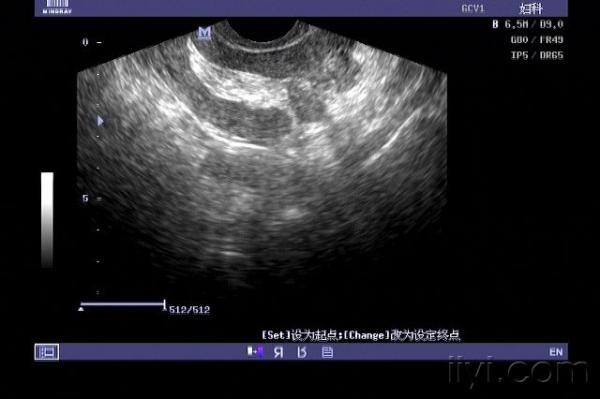

子宫穿孔超声表现图

子宫穿孔超声表现图,子宫穿孔超声图片

子宫穿孔的超声诊断

子宫穿孔超声图片

子宫穿孔彩超图

子宫穿孔b超图片